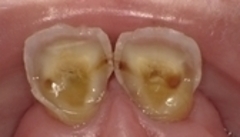

「酸しょく症」とは

酸によって歯の表面にある

エナメル質が溶けてしまう状態です

エナメル質は

白く透明感がありますが

溶けてくると

内側の象牙質が透けて

黄色くなってきます

見た目は

虫歯のように黒くならず

透明感が失われ

黄ばみが目立つようになります